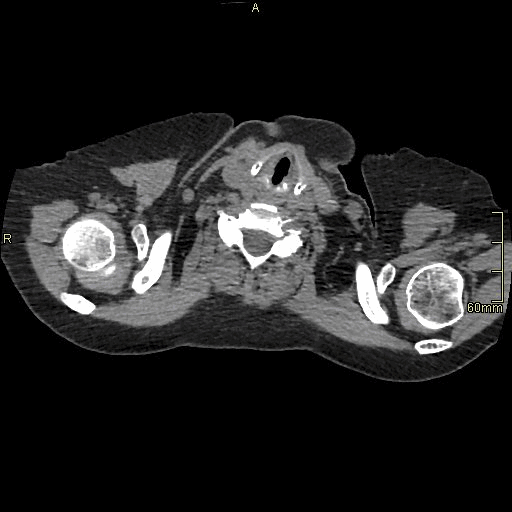

HRCT - Axial Prone Inspiration (Soft Tissue Window)